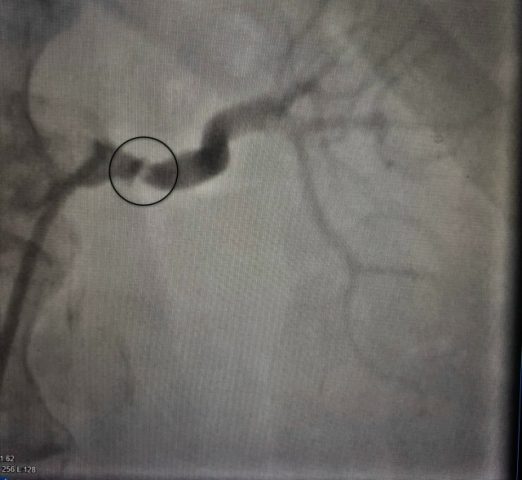

Женщину перевели в областную больницу №1, где выполнили ангиографию (контрастное исследование) почечных артерий. Результаты показали стеноз – сужение до 80%. Тогда пациентке сделали балонную ангиопластику и стентирование артерии – «расширили» артерию и установили стент. Операцию провели под руководством врача отделения рентгенхирургических методов диагностики и лечения Ивана Тимошина. Давление горожанки наконец пришло в норму, что позволило сократить количество лекарств.